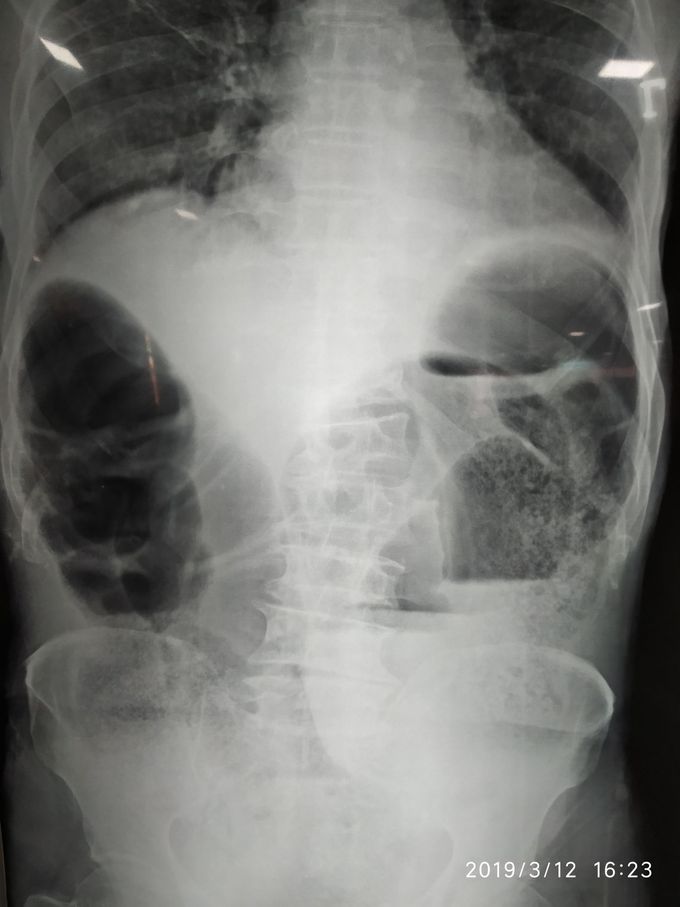

Diagosis ?

60 years male presented with Sudden onset of abdominal pain since 1 day , associated with not passing stool and urine.

Large bowel obstruction

I'm thinking on sigmoid volvulus.

Large bowel obstruction (hydroaeric levels). Scoliosis in the lombar region.

Sigmoid volvulus